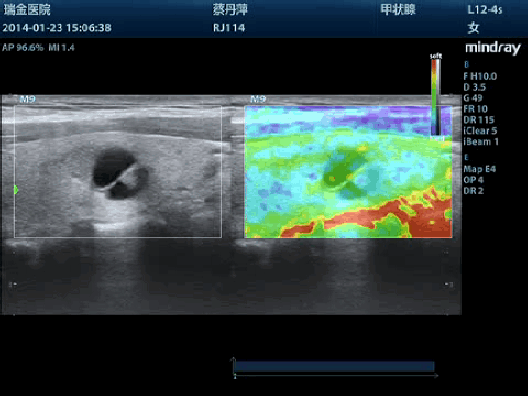

Эластография Natural Touch

Метод эластографии с имитацией естественного касания на основе новейшей запатентованной технологии Mindray делает результаты исследования менее зависимыми от наличия соответствующих навыков у пользователя, тем самым повышая точность исследования в сложных клинических условиях.

Эффективное выявление уплотнений

Стабильно высокая воспроизводимость результатов исследования